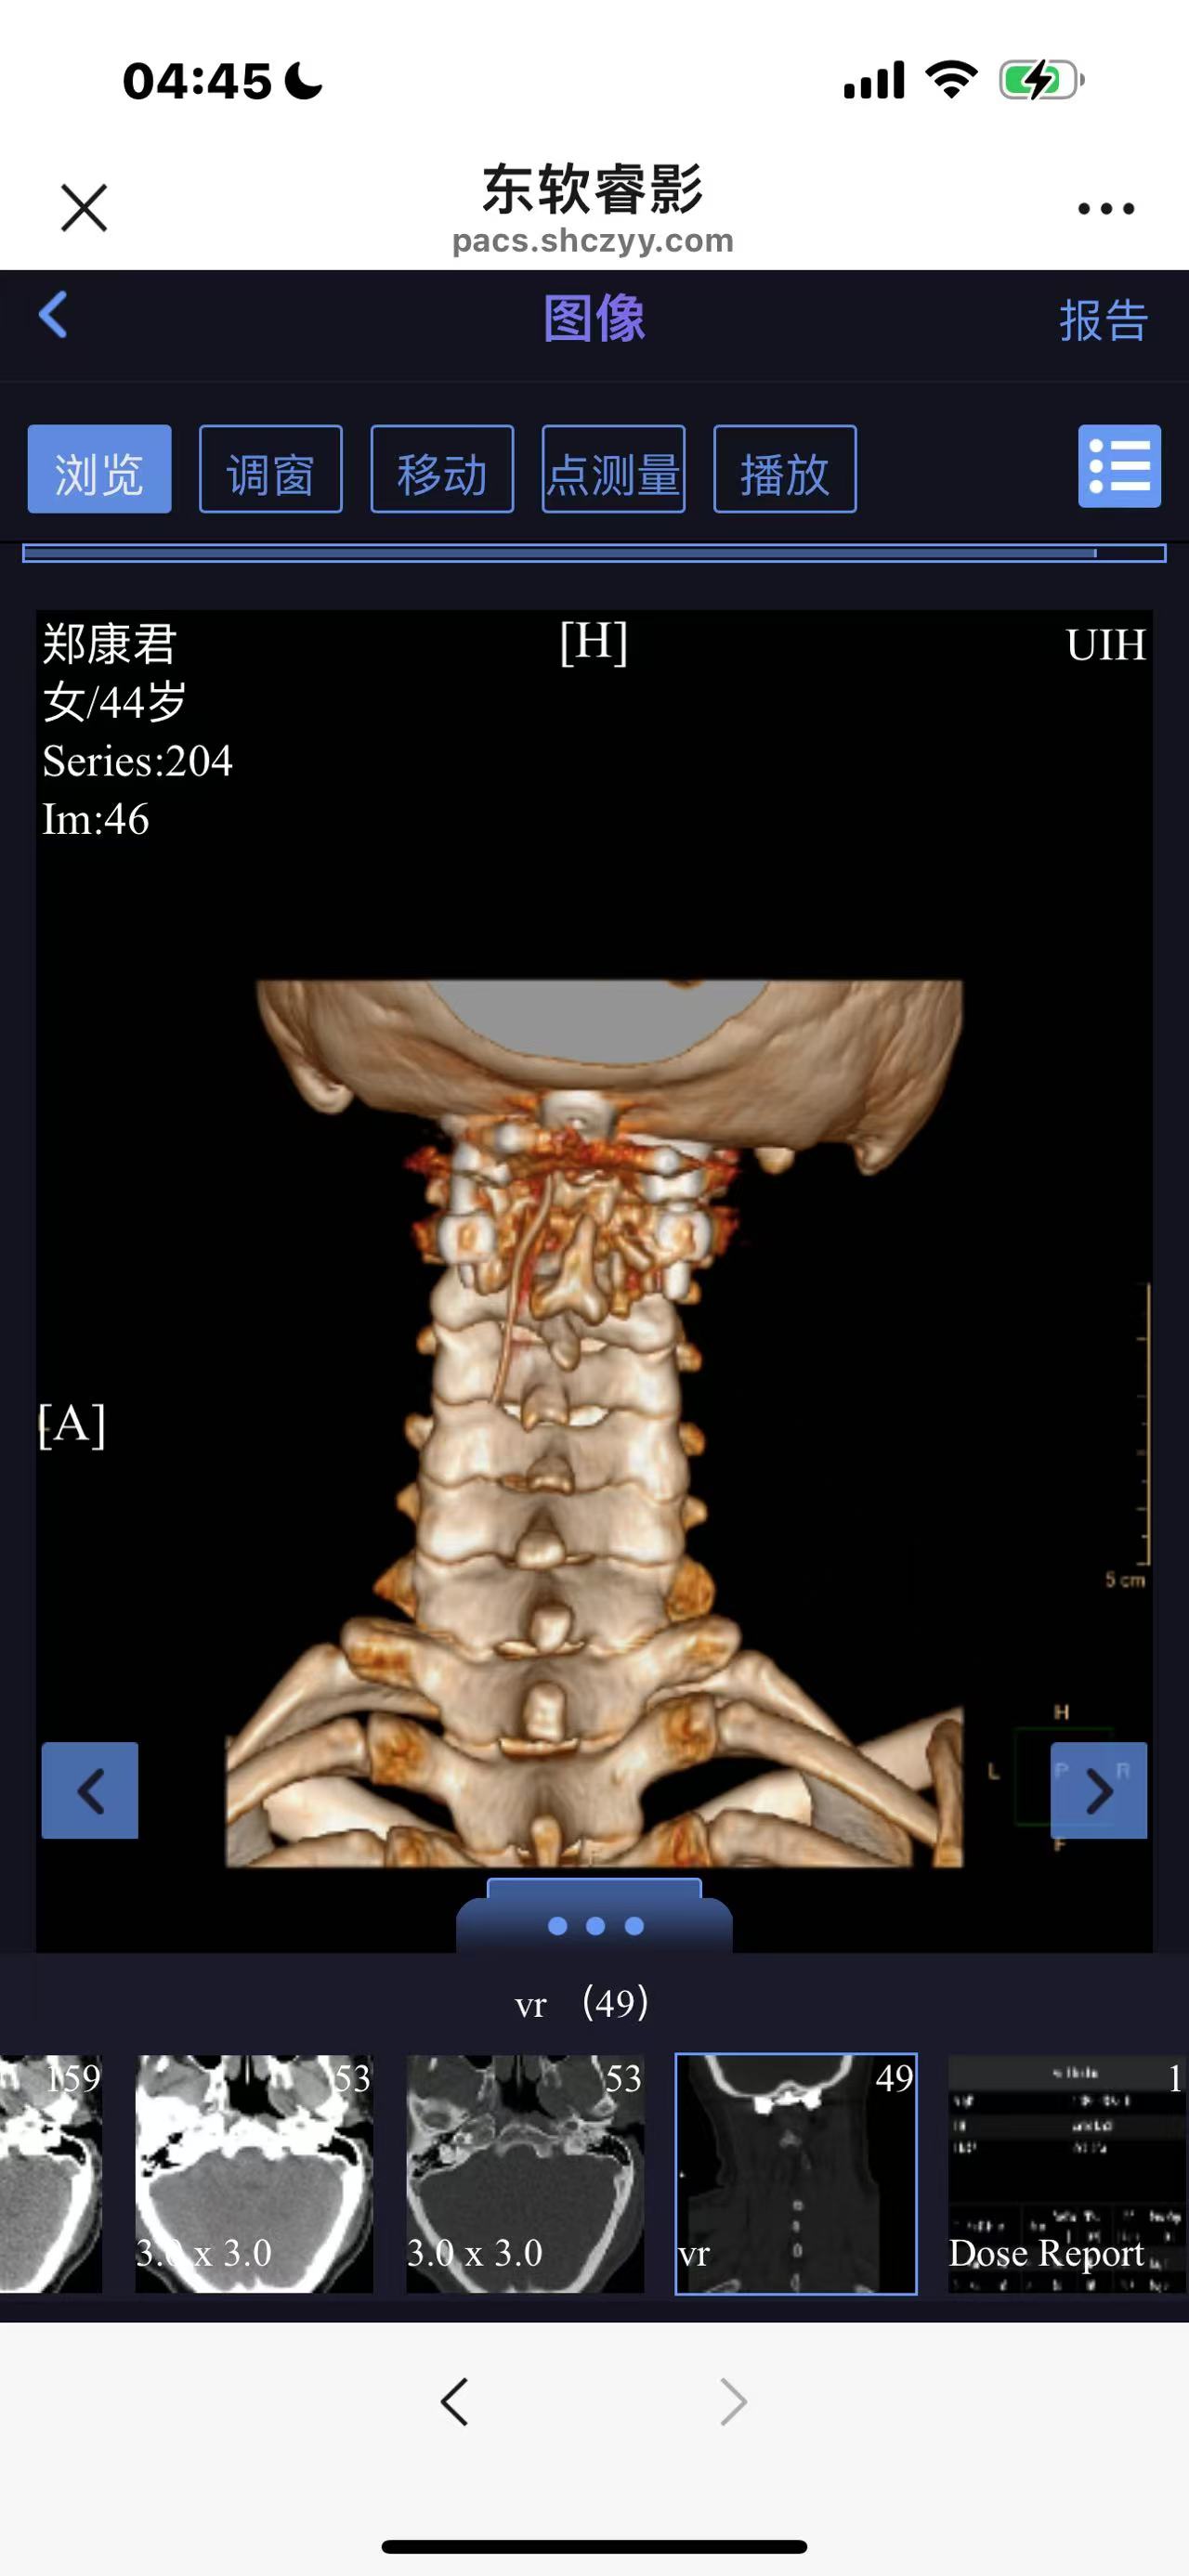

• 诊断:寰枢椎脱位

• 影像:

• 术后影像: